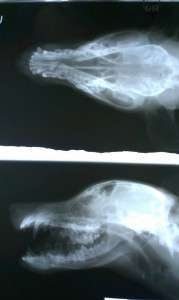

She was wondering on the streets looking for a human with a soul to love her and in return she’ll offer all her love and loyalty. In this way she found a bastard homeless who beaten her till broken her jaw, she has legs problems and who knows what we’ll still discover during investigations but she, kind and loyal soul, was standing and enduring all this treatment without leaving his side unless she was going to look for food when she was hungry. In this way it was succeeded to capture her and now she’s safe, at the clinic, where she’ll receive all the necessary care till she’ll be well in order to take her in our sanctuary from where she’ll leave only to a family that will truly love her.

Sanny has had a successful operation to repair her jaw- all went well. Now she has a long recovery ahead of her.Now is a time for patience and love as we feed her soft food slowly. In the long run, I hope all will go well for Sanny.

We have to let Sanny recover from her jaw operation to address the other health issues she faces such as her legs, etc.